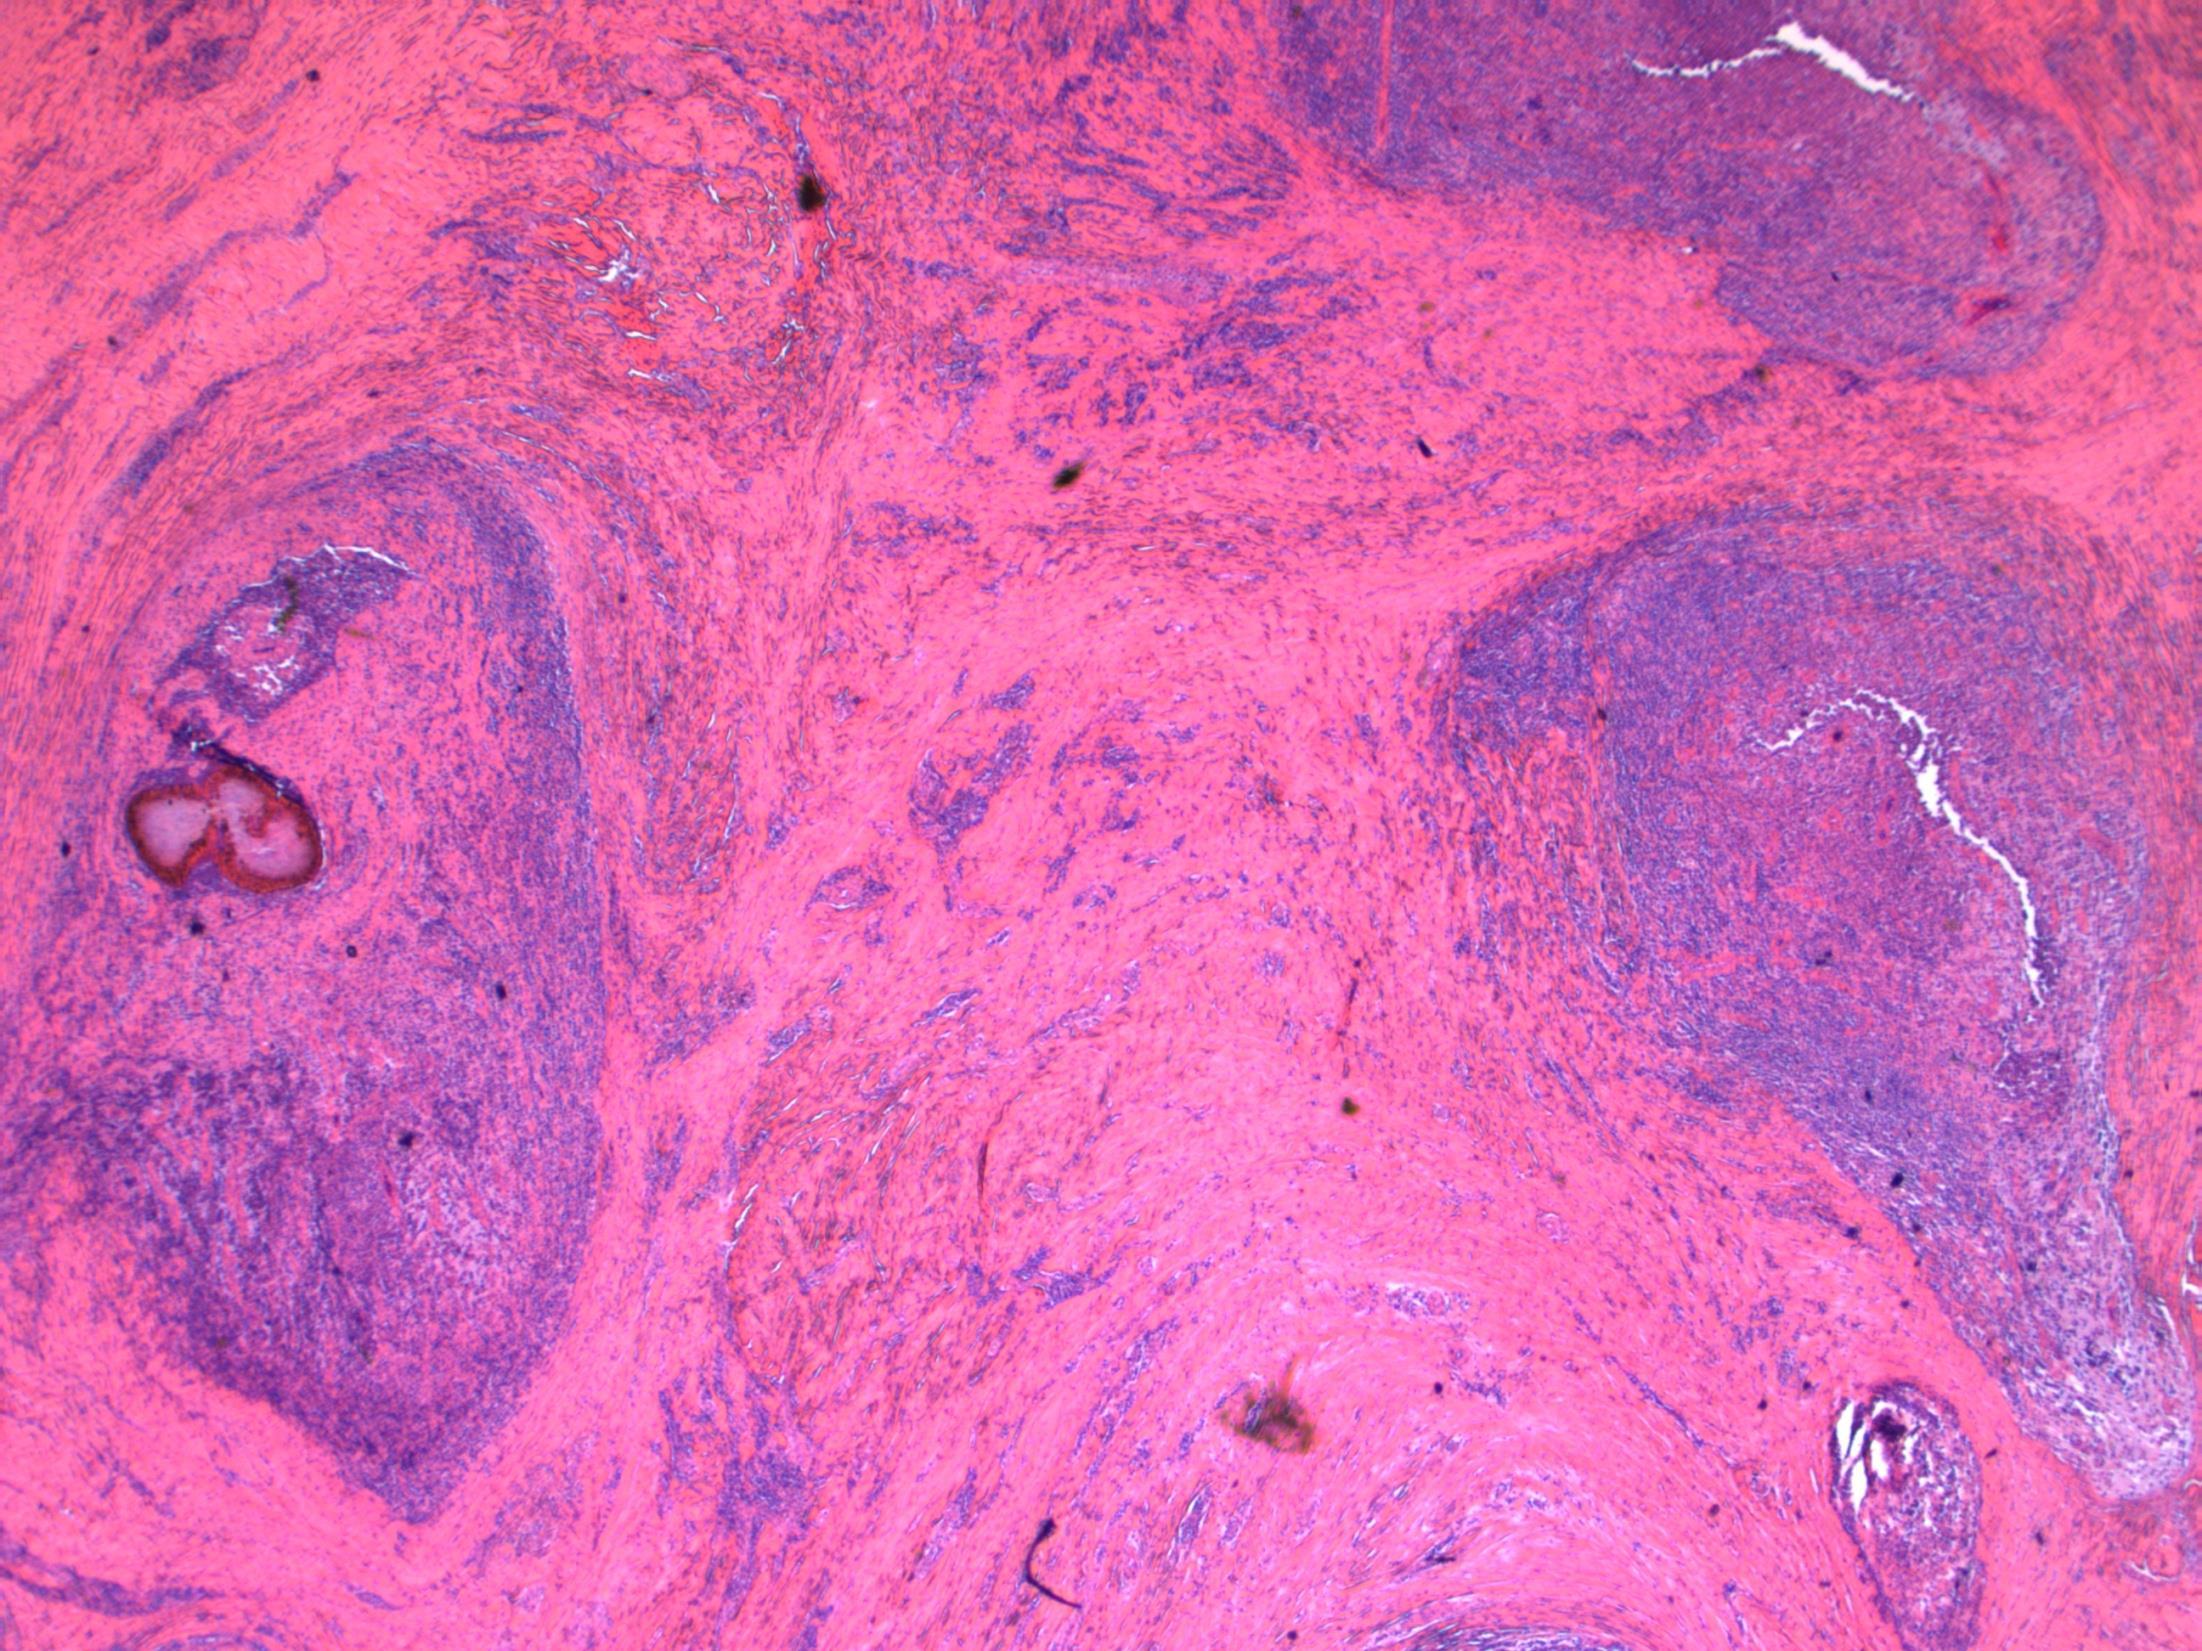

• 80F, with haematuria. Cystoscopy shows a large tumour on the posterior wall. TURBT performed.

Case 5

TURBT - G3 (high-grade) TCC with small cell carcinoma component

Case

5

AE1/3 - TCC AE1/3 – small cell CD56 - TCC CD56 – small cell

cell

- TCC

P63 - TCC

Synapto

small

P63

small cell

G3 (high-grade) TCC with small cell carcinoma component

Description: Biphasic malignant tumour. High grade large epithelial cell component and high grade small round blue cell tumour component. CIS also seen.

Favoured Diagnosis: G3 (high-grade) TCC with small cell carcinoma component. Plan: Correlate with urine cytology/ previous biopsies. IHC: TCC= AE1/3+, p63+, small cell ca = AE1/3 dot +, CD56+, synapto +. Look for invasion into lamina propria and muscle (staging).

Comments: • Small cell carcinoma is frequently admixed with TCC, SCC or adenocarcinoma of bladder • >90% muscle invasive and metastases common, poor prognosis. • Responds to chemotherapy (cisplatin based) • Differential Diagnosis of pure small cell carcinoma: – Poorly-differentiated urothelial carcinoma – Metastatic small cell carcinoma from other site eg lung – Lymphoma – Alveolar rhabdomyosarcoma – Inflammation (in a crushed, cauterised, superficial or scant specimen)

3.5 Associations, prognosis, treatment etc 3.0 Use of IHC for confirmation 2.5 Description with diagnosis, mentions both components 2.0 Only one component mentioned 1.5 Other malignant diagnosis 1.0 Benign diagnosis Case 5